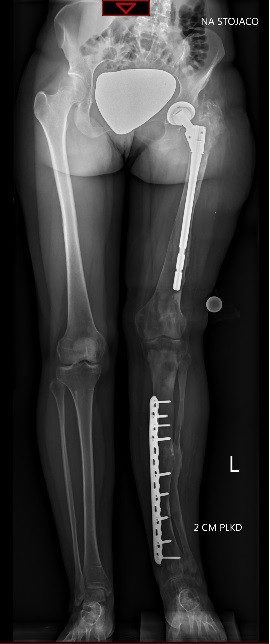

Jestem w trakcie kilkuetapowego leczenia w Paley European Institute. Przeszłam 18 operacji ortopedycznych.

Choruję na dysplazję włóknistą. Jest to rzadka choroba rozrostowa kości. Na tle wszystkich łagodnych nowotworów kości, stanowi około 7 procent spośród nich.